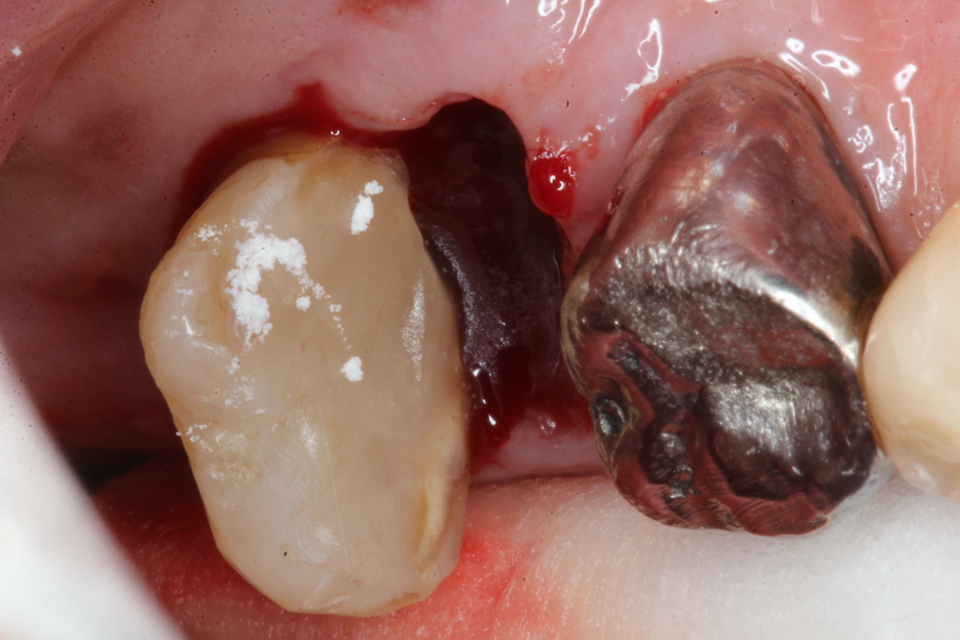

70代男性、左下7、歯根破折、自発痛++

今日は破折した歯根の接着面を新鮮面を出しきれいにしてスーパーボンドの筆積み法で貼り合わせポストを入れてCR併用で再建し、抜歯窩に挿入固定するだけだ。

根管充填材と歯質との間には隙間が存在し、細菌の代謝産物の黒色物質のFeSで覆われている。緊密な充填など絵に描いた餅にすぎない。

遠心根の切断面もスーパーボンド+CRで覆っておく